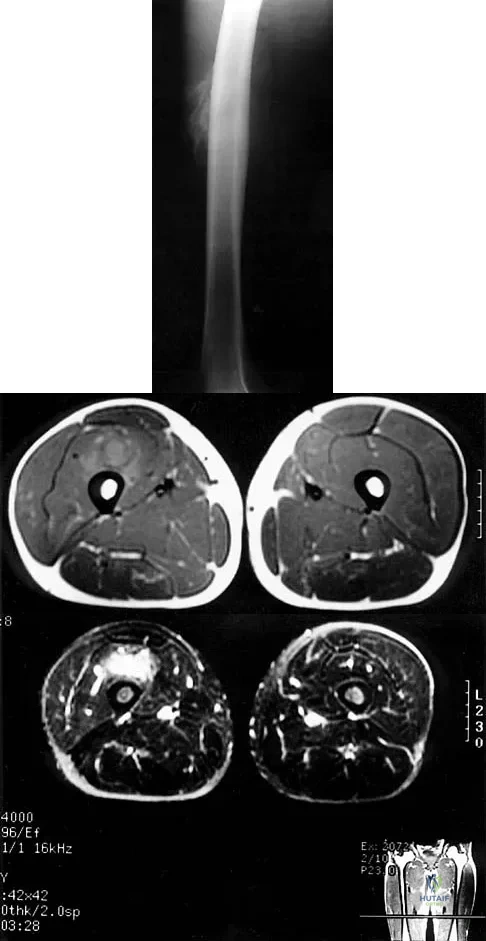

Figures 30a and 30b show the MRI scans of a 51-year-old woman who has had an enlarging soft-tissue mass in her right thigh for the past 18 months. Examination reveals no inguinal adenopathy. Results of a biopsy show a high-grade sarcoma. A bone scan is unremarkable, and a CT scan of the chest shows no evidence of pulmonary metastasis. According to the Musculoskeletal Tumor Society (MSTS) staging system, the tumor should be classified as what stage?

According to the MSTS staging system, soft-tissue sarcomas are staged according to the following factors: grade, site, and metastasis. Roman numerals are used to designate malignant tumors, and Arabic numerals are used for benign tumors. Low-grade malignant tumors are staged as I while intermediate- and high-grade tumors are staged as II. Site is defined as intracompartmental (A) or extracompartmental (B). Any metastasis is staged as III. This patient has a high-grade tumor (II), and the MRI scans show that it is confined to a single compartment; therefore, it is staged as IIA. There is no evidence of metastatic disease. Enneking WF, Spanier SS, Goodman MA: A system for the surgical staging of musculoskeletal sarcoma. Clin Orthop 1980;153:106-120. Peabody TD, Monson D, Montag A, Schell MJ, Finn H, Simon MA: A comparison of the prognoses for deep and subcutaneous sarcomas of the extremities. J Bone Joint Surg Am 1994;76:1167-1173. Pisters PW, Leung DH, Woodruff J, Shi W, Brennan MF: Analysis of prognostic factors in 1,041 patients with localized soft tissue sarcomas of the extremities. J Clin Oncol 1996;14:1679-1689.